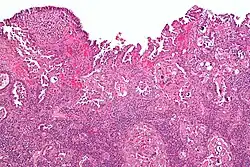

| Histology H&E of uterine serous papillary carcinoma. H&E stain. | |

Histopathologically, uterine serous carcinomas is typically characterized by (1) nipple-shaped structures (papillae) with fibrovascular cores (2) marked nuclear atypia (irregularities in the nuclear membrane, enlarged nuclear size), (3) psammoma bodies and (4) cilia. These are general findings in serous tumors which are also seen in such tumors in other anatomic locations.